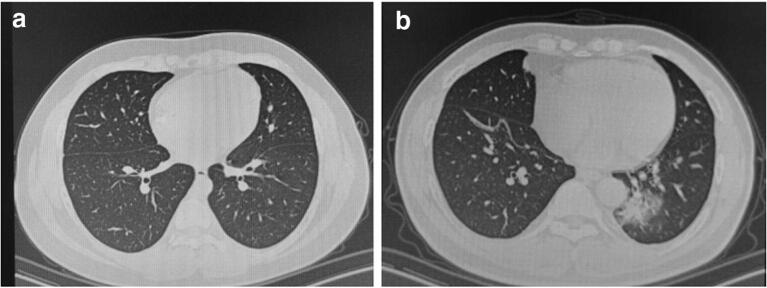

Fig. 1.

a Unenhanced CT images of Case 1 showing normal results; b Unenhanced CT images of Case 1’s father showing bilateral pneumonia with ground-glass opacities especially in the left lung

His family members displayed similar symptoms. His father had a low fever of 37.8 °C for one day, with no cough or other discomforts. His mother had a mild cough for one week without fever. His father's chest CT showed bilateral pneumonia with ground-glass opacities especially in the left lung (Fig. 1b), and his mother's chest CT was normal. They both tested positive for SARS-CoV-2.